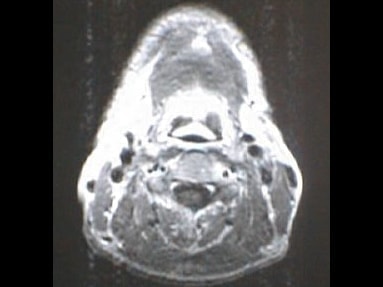

MRI画像比較

入院当時MRI画像②

入院3か月後癌消滅MRI画像②